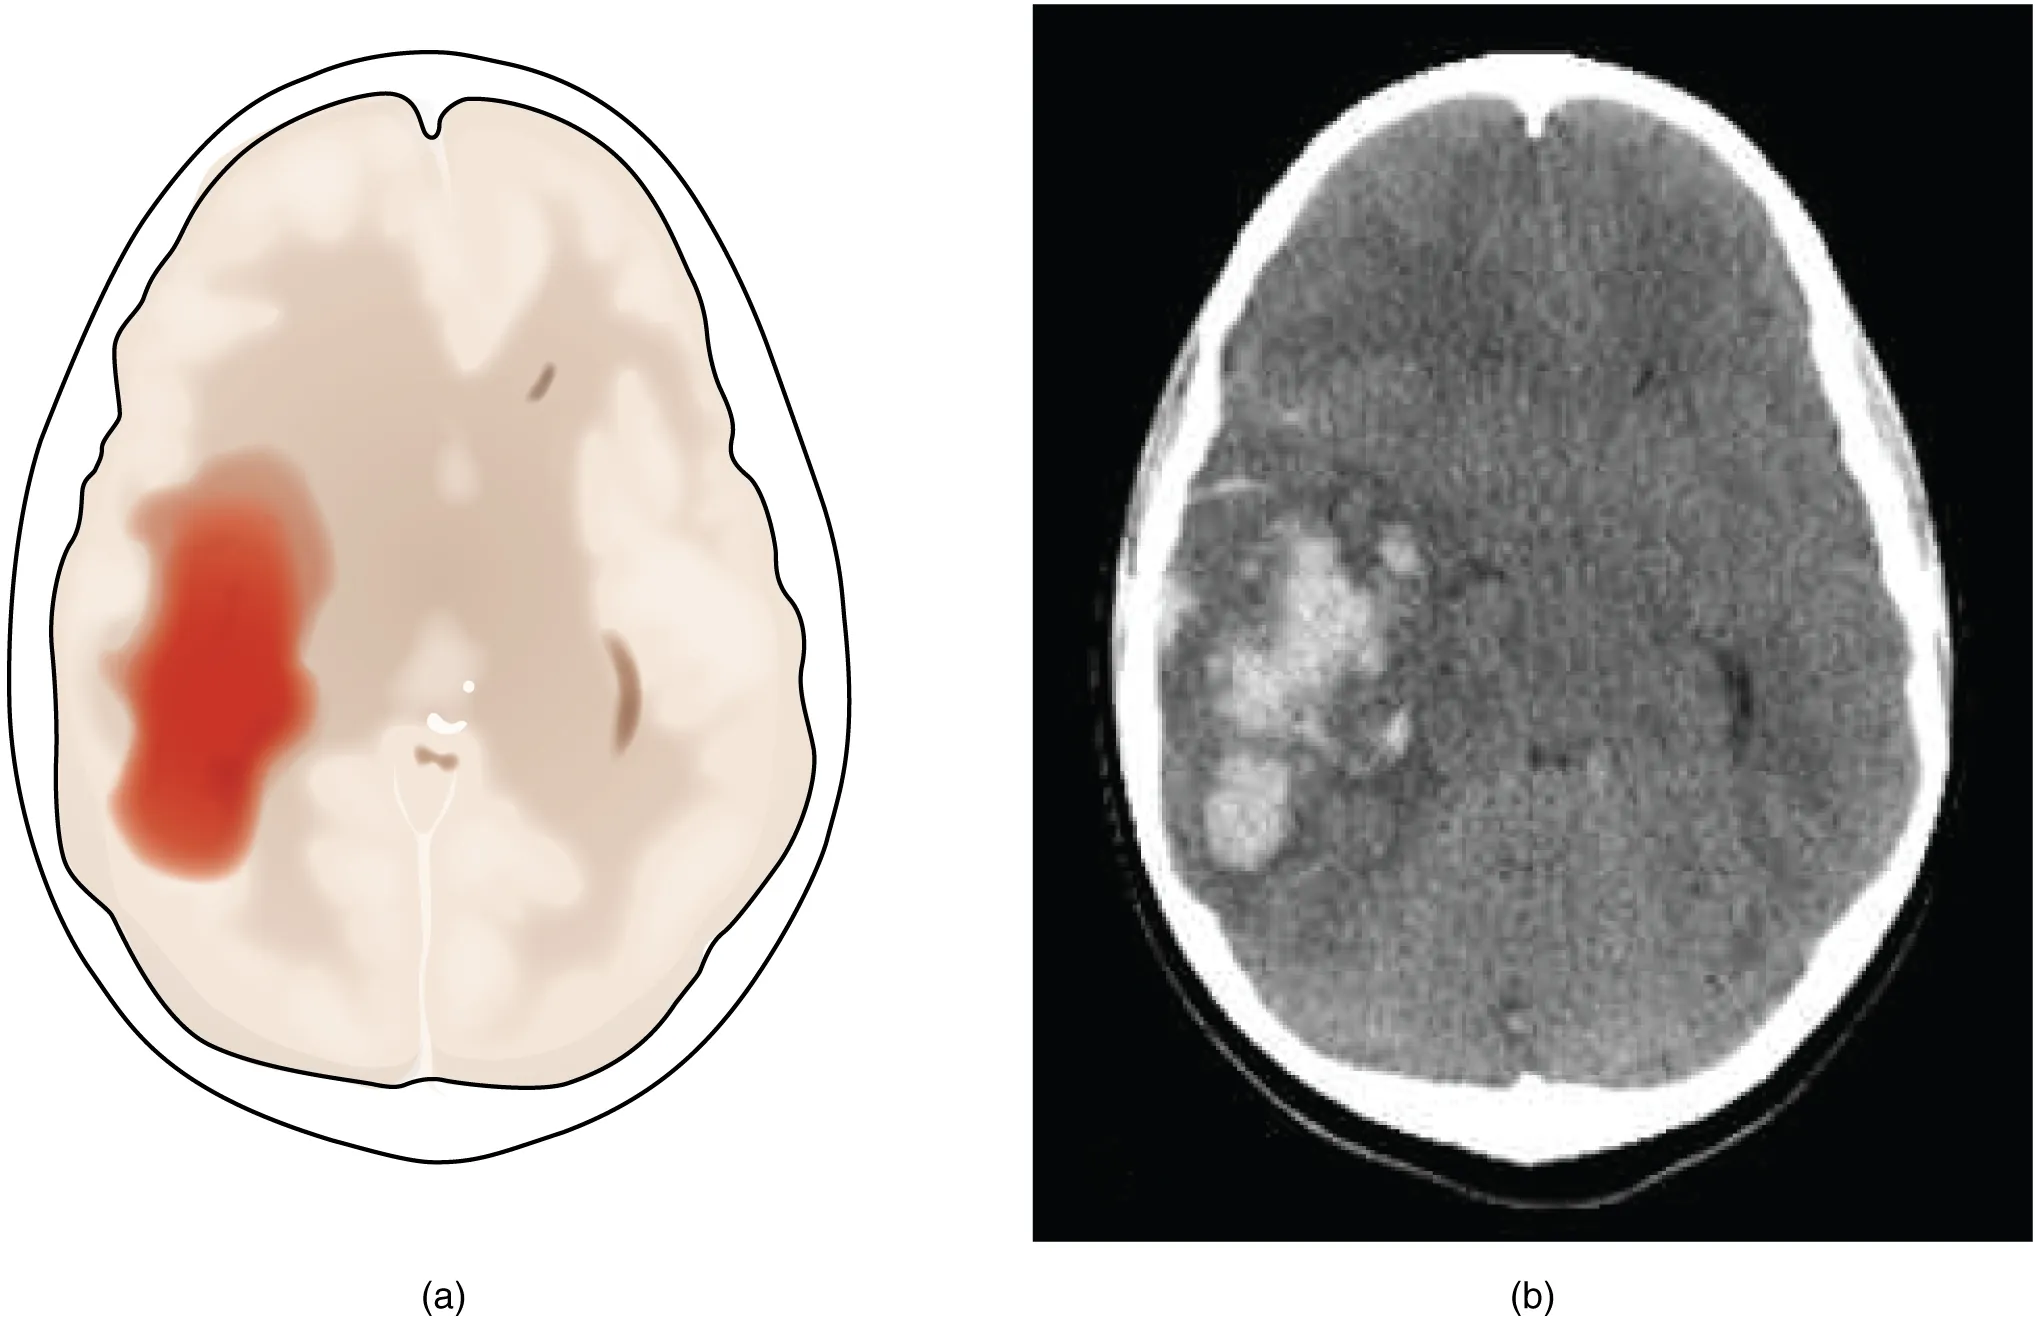

A hemorrhagic stroke is bleeding into the brain because of a damaged blood vessel. Accumulated blood fills a region of the cranial vault and presses against the tissue in the brain (Figure 16.3). Physical pressure on the brain can cause the loss of function, as well as the squeezing of local arteries resulting in compromised blood flow beyond the site of the hemorrhage. As blood pools in the nervous tissue and the vasculature is damaged, the blood-brain barrier can break down and allow additional fluid to accumulate in the region, which is known as edema.

The left panel of this image shows an image of the brain with a region in red. Arrows pointing towards this region indicate a hemorrhage associated with a stroke. The right panel shows a hemorrhage as it might appear on a CT scan.

Figure 16.3 Hemorrhagic Stroke (a) A hemorrhage into the tissue of the cerebrum results in a large accumulation of blood with an additional edema in the adjacent tissue. The hemorrhagic area causes the entire brain to be disfigured as suggested here by the lateral ventricles being squeezed into the opposite hemisphere. (b) A CT scan shows an intraparenchymal hemorrhage within the parietal lobe. (credit b: James Heilman)